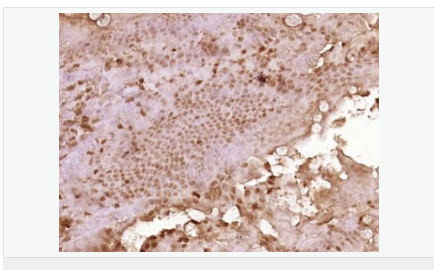

| 產(chǎn)品應(yīng)用 | WB=1:500-2000 ELISA=1:5000-10000 IHC-P=1:100-500 IHC-F=1:100-500 ICC=1:100-500 IF=1:100-500 (石蠟切片需做抗原修復(fù)) not yet tested in other applications. optimal dilutions/concentrations should be determined by the end user. |

| 產(chǎn)品介紹 | C3orf32 (chromosome 3 open reading frame 32), also known as fls485, is a 353 amino acid protein encoded by a gene that maps to human chromosome 3p26.1. Chromosome 3 is made up of approximately 214 million bases encoding over 1,100 genes. Notably, there is a chemokine receptor gene cluster and a variety of human cancer related loci on chromosome 3. Particular regions of the chromosome 3 short arm are deleted in many types of cancer cells. Key tumor suppressing genes on chromosome 3 encode apoptosis mediator RASSF1, cell migration regulator HYAL1 and angiogenesis suppressor SEMA3B. Marfan Syndrome, porphyria, von Hippel-Lindau syndrome, osteogenesis imperfecta and Charcot-Marie-Tooth disease are a few of the numerous genetic diseases associated with chromosome 3. Subcellular Location: Cytoplasm. Tissue Specificity: Expressed in enterocytes of small and large intestinal mucosa (at protein level). Expressed in enterocytes, chromaffine and interstitial cells. SWISS: Q9Y2M2 Gene ID: 51066 Database links: Entrez Gene: 51066 Human SwissProt: Q9Y2M2 Human Unigene: 561182 Human Unigene: 740735 Human Important Note: This product as supplied is intended for research use only, not for use in human, therapeutic or diagnostic applications. |